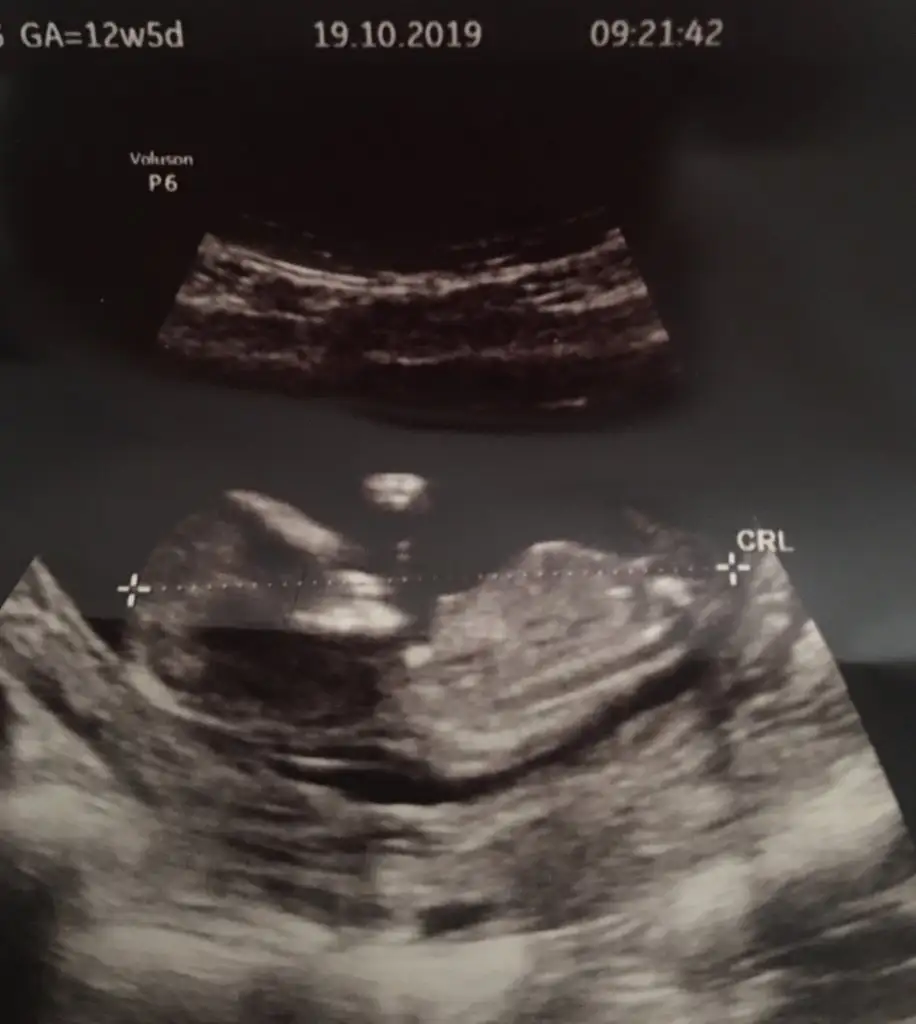

dr soylemeden siz gorun genital nub teorisi ( bebegin cinsiyeti)

Doktor kız tahmininde bulundu ama her gören erkek diyor :)

Evet erkek gibi iri bebek nubta tam dik değil kız yazacaktım .keşke görünüşüne bakmasaymışım 😂😂 saglıkla gelsin prenses 😍

Doktor tam kesin 3 hafta sonra söyleyecekmiş inşallah doktorun tahmini değişmez :)

Önceliğim sağlıklı olması ama kız deyince hemen alışıverdim :))